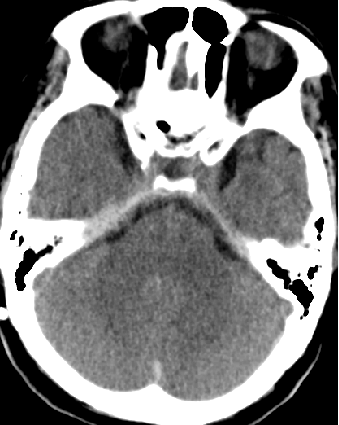

2015-3-31

脑压100

2015-4-1 MRI

诊断